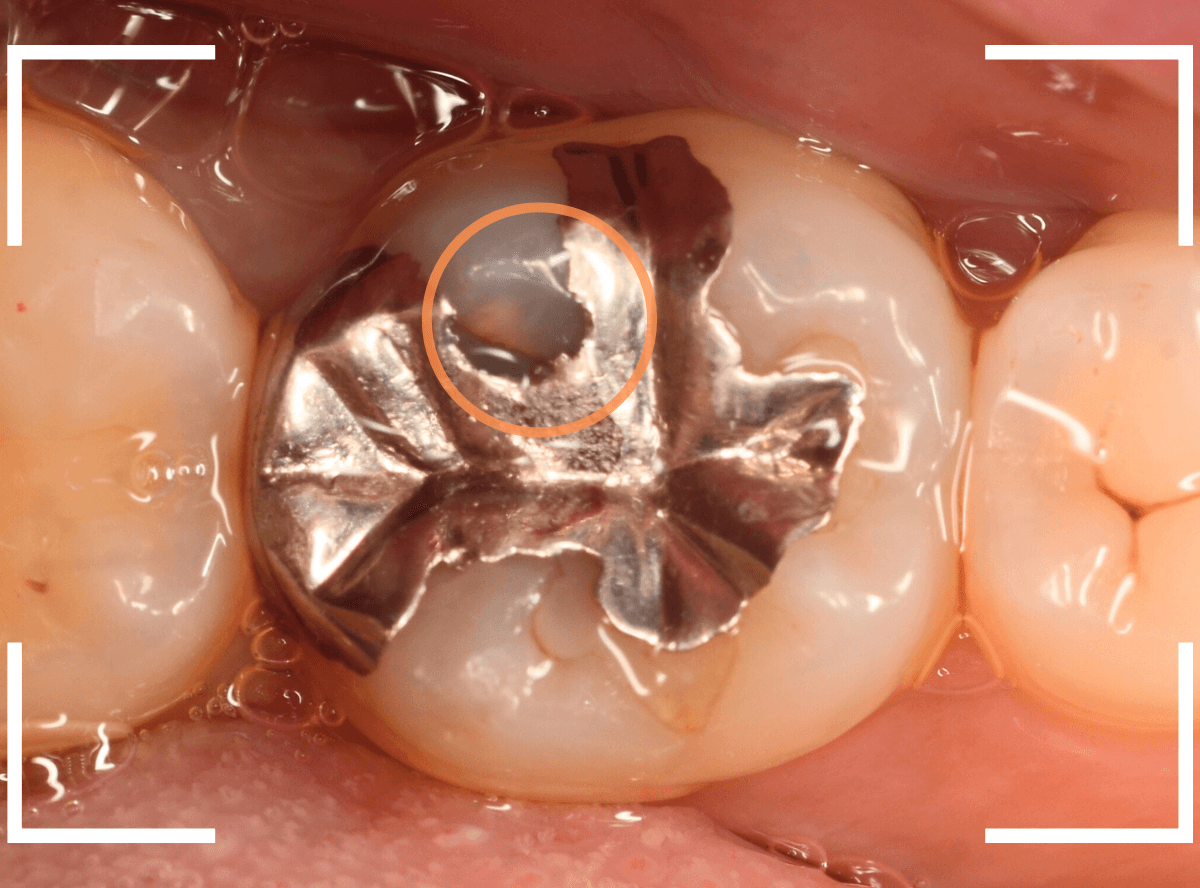

Case.12 検診で見つかった、インレーの下の深い虫歯

検診目的で来院された患者さんです。

特に気になるところもなかったですが、検査をすると、お口の中の色々な部分に虫歯が見つかりました。

その中の一か所、上の奥歯のインレーの下の虫歯です。

見た目だけでははっきりわかりませんでしたが、レントゲン写真で確認すると、インレーの下で虫歯になっているのがわかります。

インレーを除去して、治療を開始します。

ある程度、虫歯を除去したところで、う蝕検知液で確認します。

赤い部分が虫歯です。

やはり、レントゲン写真で確認した部分が深めの虫歯になっていたようです。

全ての虫歯を除去しました。

お薬をつめて痛みやしみが出ないか、しばらく経過観察しますが、おそらく大丈夫でしょう。

症状が出る前に、検診に来ていただいたことで最小限の治療で済みました。